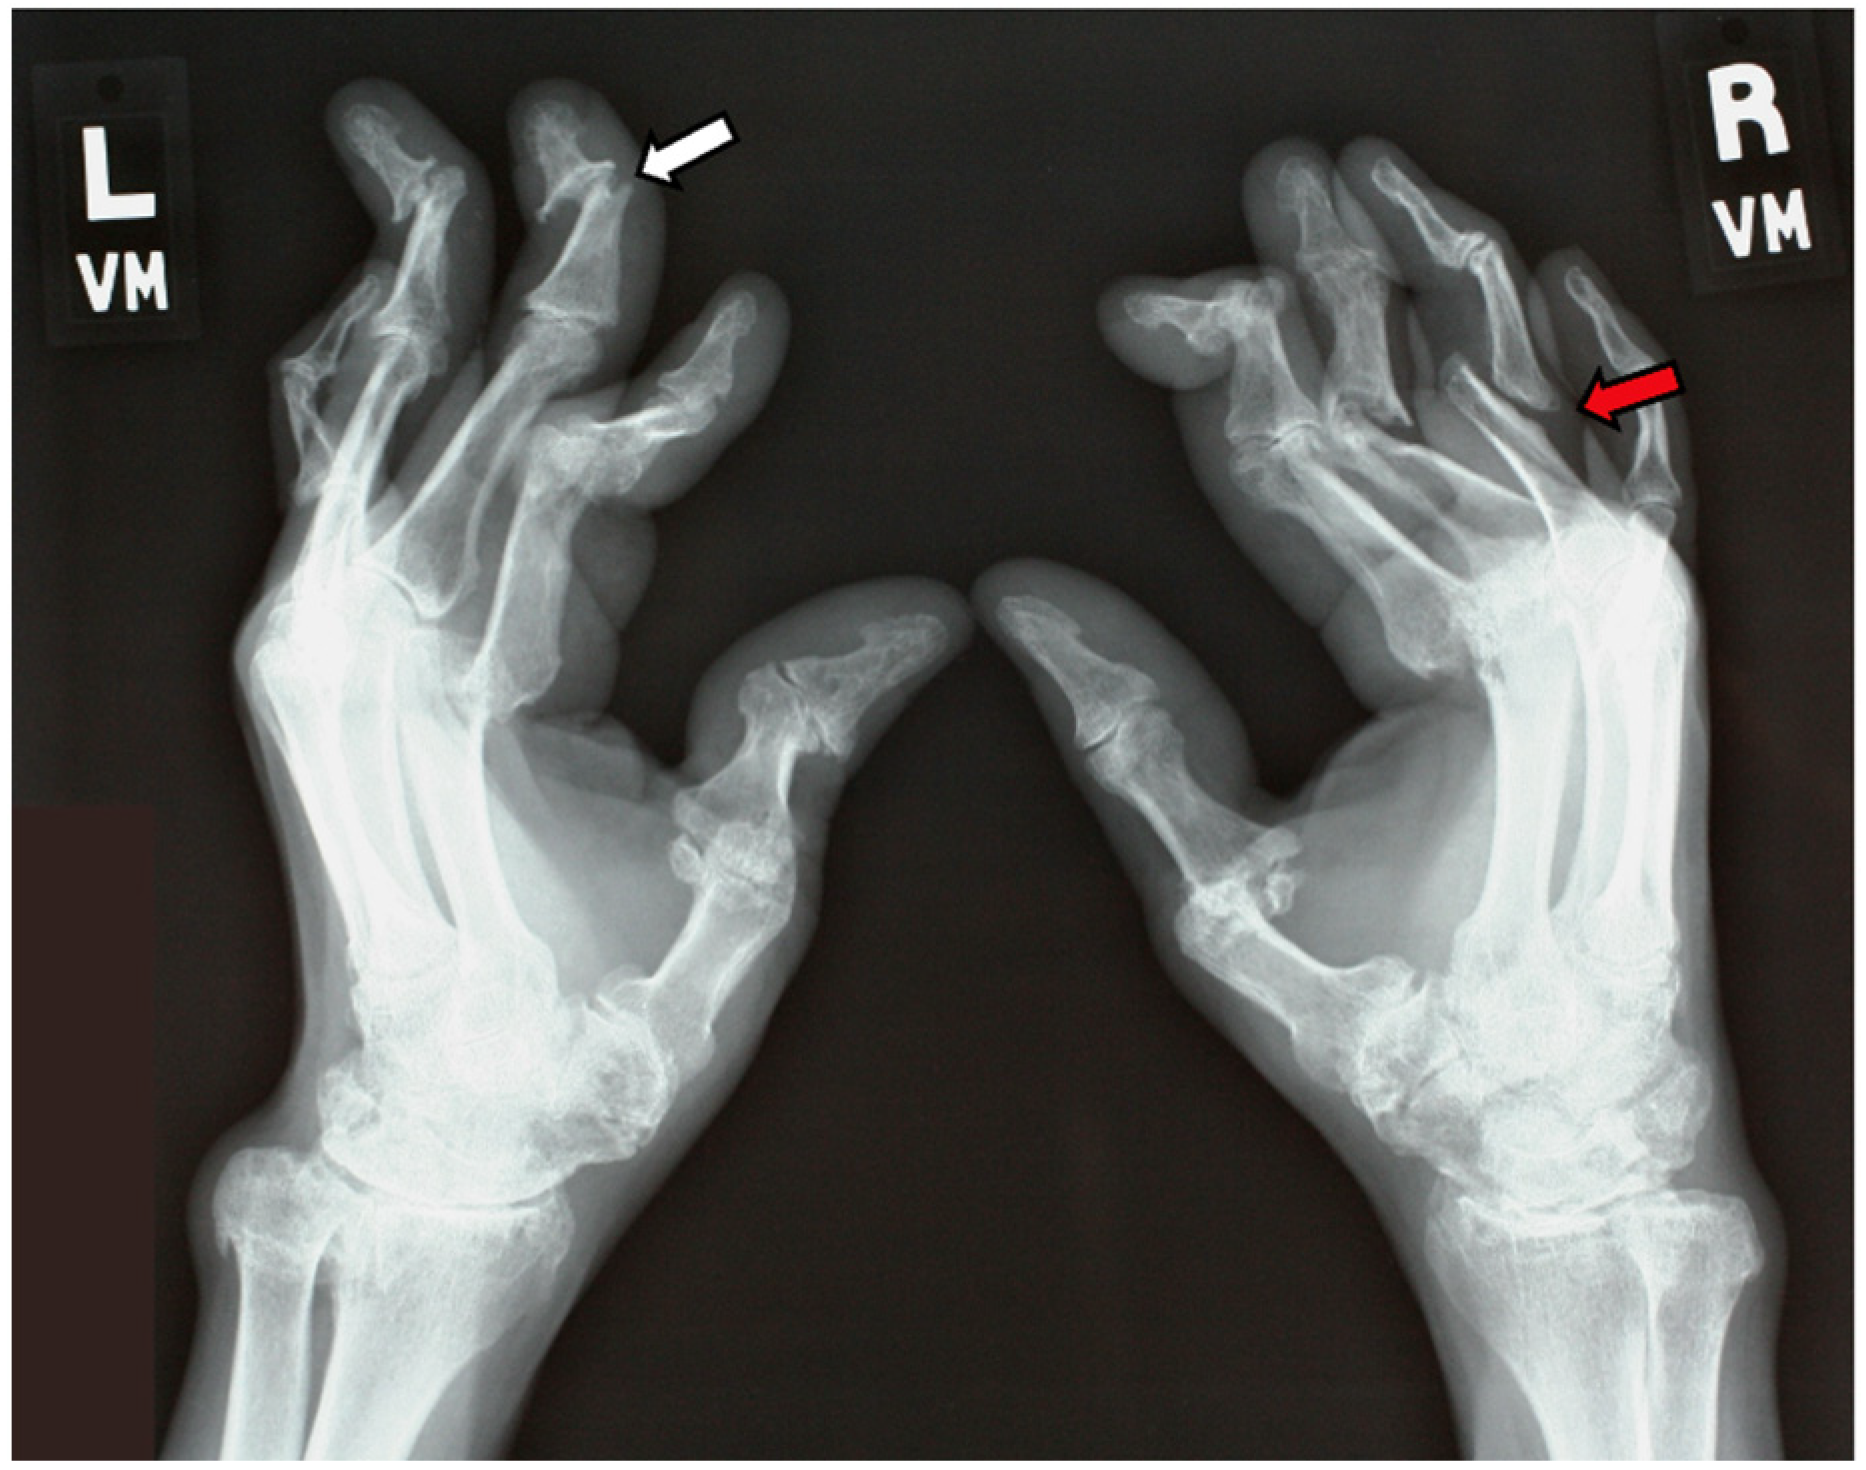

7.2.1. Plain Radiographs